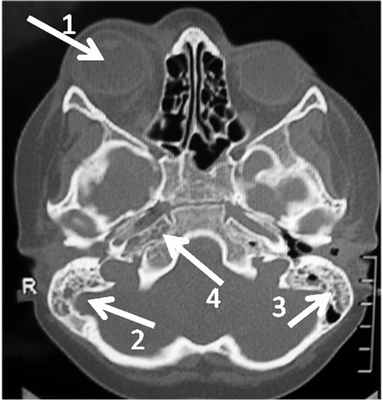

Больной А., 6 лет, поступил в ЛОР-отделение ДРКБ 24.09.14 с жалобами на сильную головную боль в правой половине головы, обильное гноетечение из обоих ушей, невозможность открыть правый глаз, снижение зрения на правый глаз, вялость, слабость, повышение температуры до 38—39°С. Заболел остро 17.09.14, когда появились температура до 39 °C и сильная головная боль. Педиатр поставил диагноз ОРВИ, было назначено симптоматическое лечение. 20.09.14 появилась боль в ушах, а 21.09.14 — обильное гноетечение из обоих ушей. 22.09.14 больной обратился в районную больницу Бугульмы и был госпитализирован в инфекционное отделение. Начато лечение: инъекции цефтриаксона и ушные капли 2,6% рифампицина натрия. К вечеру того же дня появился экзофтальм справа, гиперемия, отек век правого глаза. 24.09.14 в экстренном порядке направлен в ДРКБ МЗ Р.Т. Казани. При поступлении больной вялый, температура до 38 °C, не сидит, имеются менингеальные знаки: симптом Кернига и ригидность затылочных мышц. Испытывает боль при дотрагивании до головы. Правый глаз закрыт, экзофтальм, гиперемия, отек век, хемоза нет. Нос и зев без патологии. Наружные слуховые проходы с обеих сторон заполнены сероватым гноем, барабанные перепонки мутные, серорозовые, отечны, перфорации в передних отделах. Общий анализ крови (ОАК): лейкоцитоз до 21·10 9 /л, резкий сдвиг влево, СОЭ 54 мм/ч, С-реактивный белок (СРБ) 11,44 мг/дл. Коагулограмма: фибриноген 7,9 г/л, ПТИ — 50%, МНО 1,45, АЧТВ и ТВ — нет коагуляции. Прокальцитонин 1,72 нг/мл. Осмотрен нейрохирургом, офтальмологом, педиатром. Глазное дно: диски зрительного нерва стушеваны, границы нечеткие. На рентгеновской компьютерной томографии (РКТ) височных костей и головного мозга — снижение пневматизации клеток сосцевидного отростка с обеих сторон и клеток каменистой части височных костей справа, томографические признаки тромбоза кавернозного синуса и правой глазничной вены, сужение и признаки тромбоза правой внутренней сонной артерии, утолщение зрительного нерва справа, накопление контраста оболочками височной доли на границе с кавернозным синусом. Пневматизация околоносовых пазух не нарушена (рис. 1).

Рис. 1. РКТ височных костей в аксиальной проекции от 24.09.14. 1 — экзофтальм правого глаза; 2, 3 — снижение пневматизации обоих сосцевидных отростков с очагами деструкции; 4 — снижение пневматизации клеток каменистой части височной кости справа с очагами деструкции.